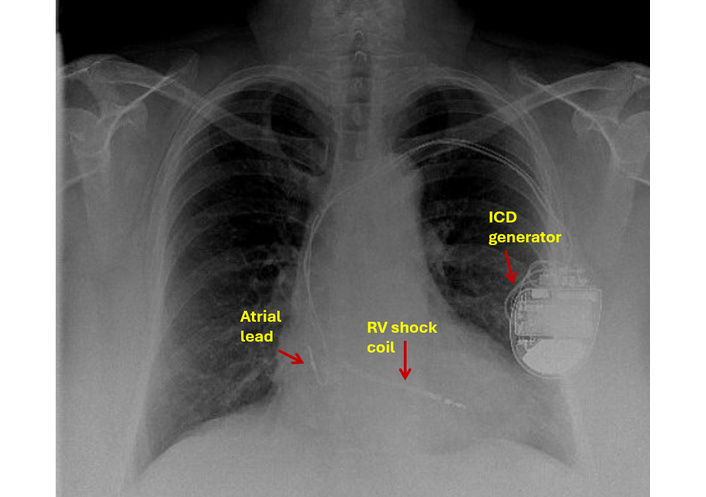

An antero-posterior (AP) chest radiograph (Figure 3) was reported as satisfactory; however, a lateral projection was not obtained.

Chest X-ray: antero-posterior view showing ICD lead in an apparently good position. ICD: implantable cardioverter defibrillator; RV: right ventricle.